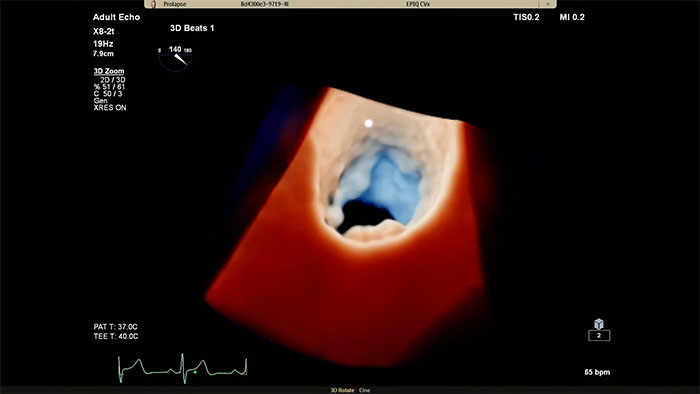

Visualize cardiac morphology using ultrasound with TrueVue Glass